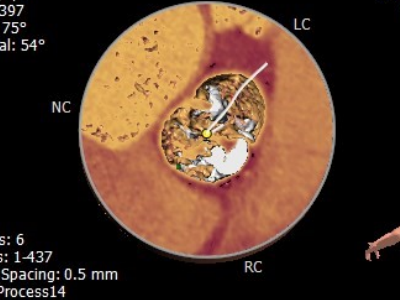

主动脉瓣钙化分布

• 主动脉瓣重度钙化,钙化主要分布于瓣叶及瓣叶交界处;钙化从瓣环延伸至流出道9.7mm;